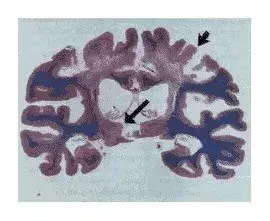

随后科学家研究了 Quinlan 的大脑和脊髓,研究结果发表在 1994 年的《新英格兰医学杂志》(NEJM)。研究发现她的大脑皮层有中度损伤,但她的丘脑两侧损伤更重,而控制呼吸和心脏功能的脑干相对完好。也就是说,丘脑在意识控制中起着特别重要的作用。

图 | Quinlan 大脑的光学显微镜图。短箭头所指是大脑皮层及下面的白质有严重萎缩,长箭头所指是丘脑两侧严重萎缩。